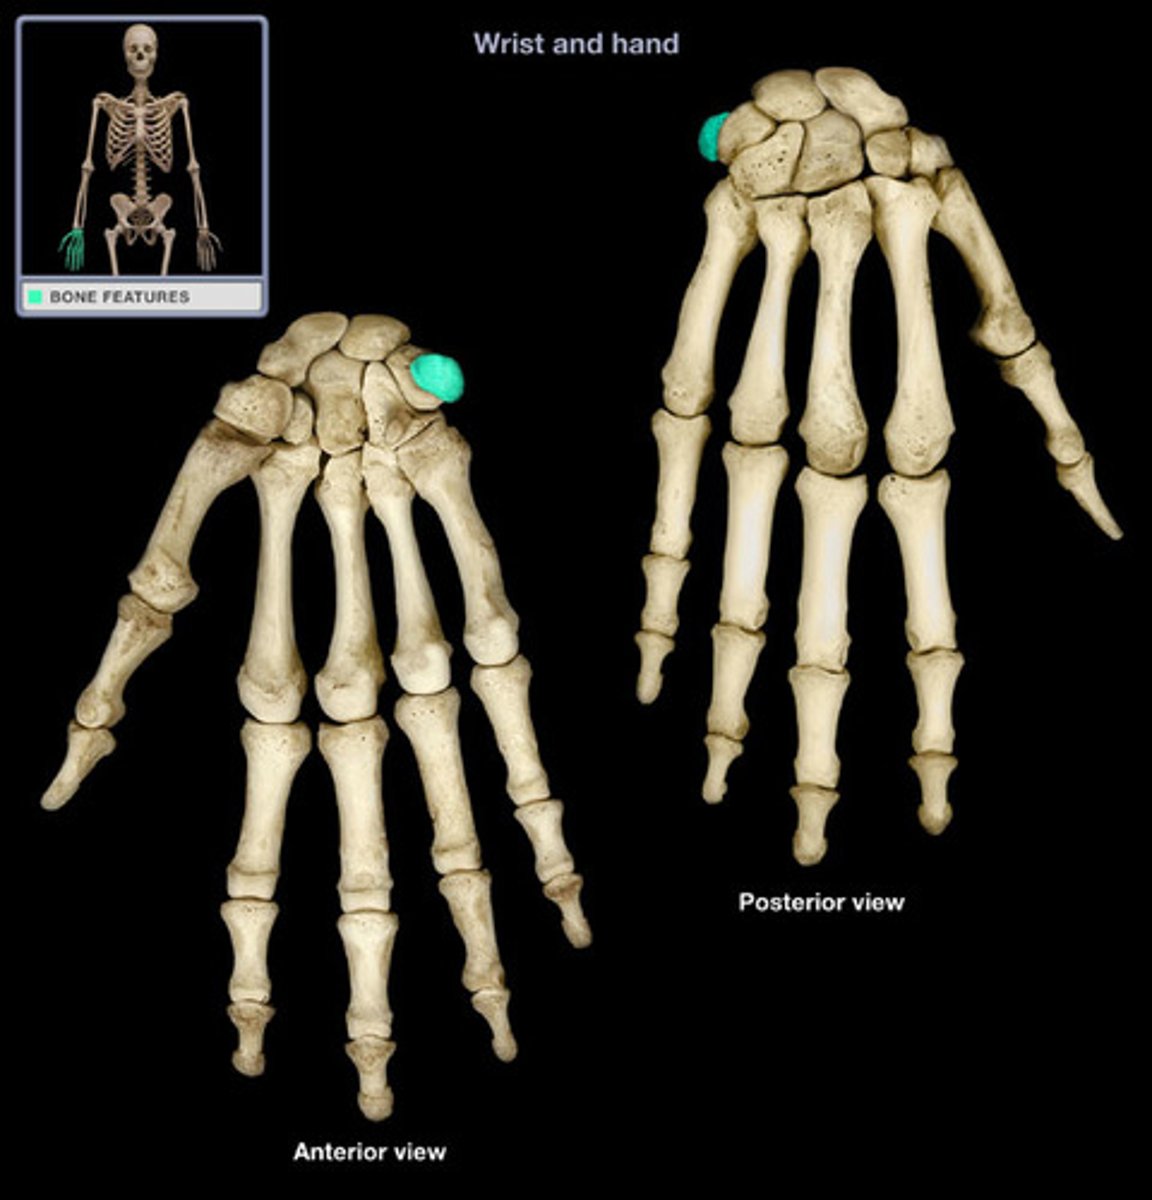

Carpal bones

scaphoid, lunate, triquetrum, pisiform, trapezium, trapezoid, capitate, hamate

Triquetrum

Name this specific bone of the hand.

Pisiform

Name this specific bone of the hand.

Trapezium

Name this specific bone of the hand.

Trapezoid

Name this specific bone of the hand.

Capitate

Name this specific bone of the hand.

Hamate

Name this specific bone of the hand.